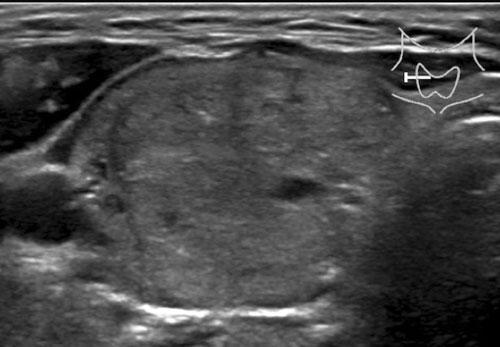

Trường hợp 3

Quan sát hình ảnh và xác định điểm TI-RADS.

Cuộn hình ảnh để xem điểm TI-RADS.

Lưu ý các tiêu điểm tăng âm nhỏ hiện diện.

Tổng cộng 6 điểm tương ứng với điểm TI-RADS là 4.